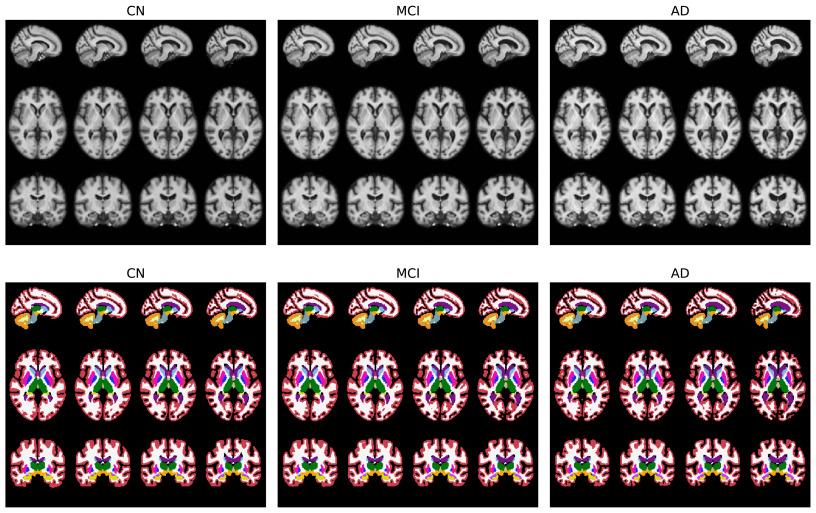

图15基于年龄、性别和认知状态属性学习的模板及其相应的分割标签。从左到右:认知正常、轻度认知障碍和阿尔茨海默病。对于每个认知组,我们展示了四个年龄增长阶段(55到90岁)的模板,并将性别固定为男性。